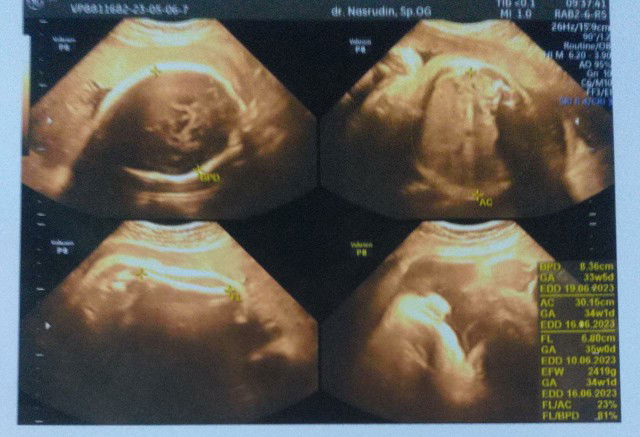

USG trimester 3

usg tm 3 di usia 34,5 minggu, bbj udah 3kg disuruh diet gula sama dokternya krna hpl masih sebulan lagi.